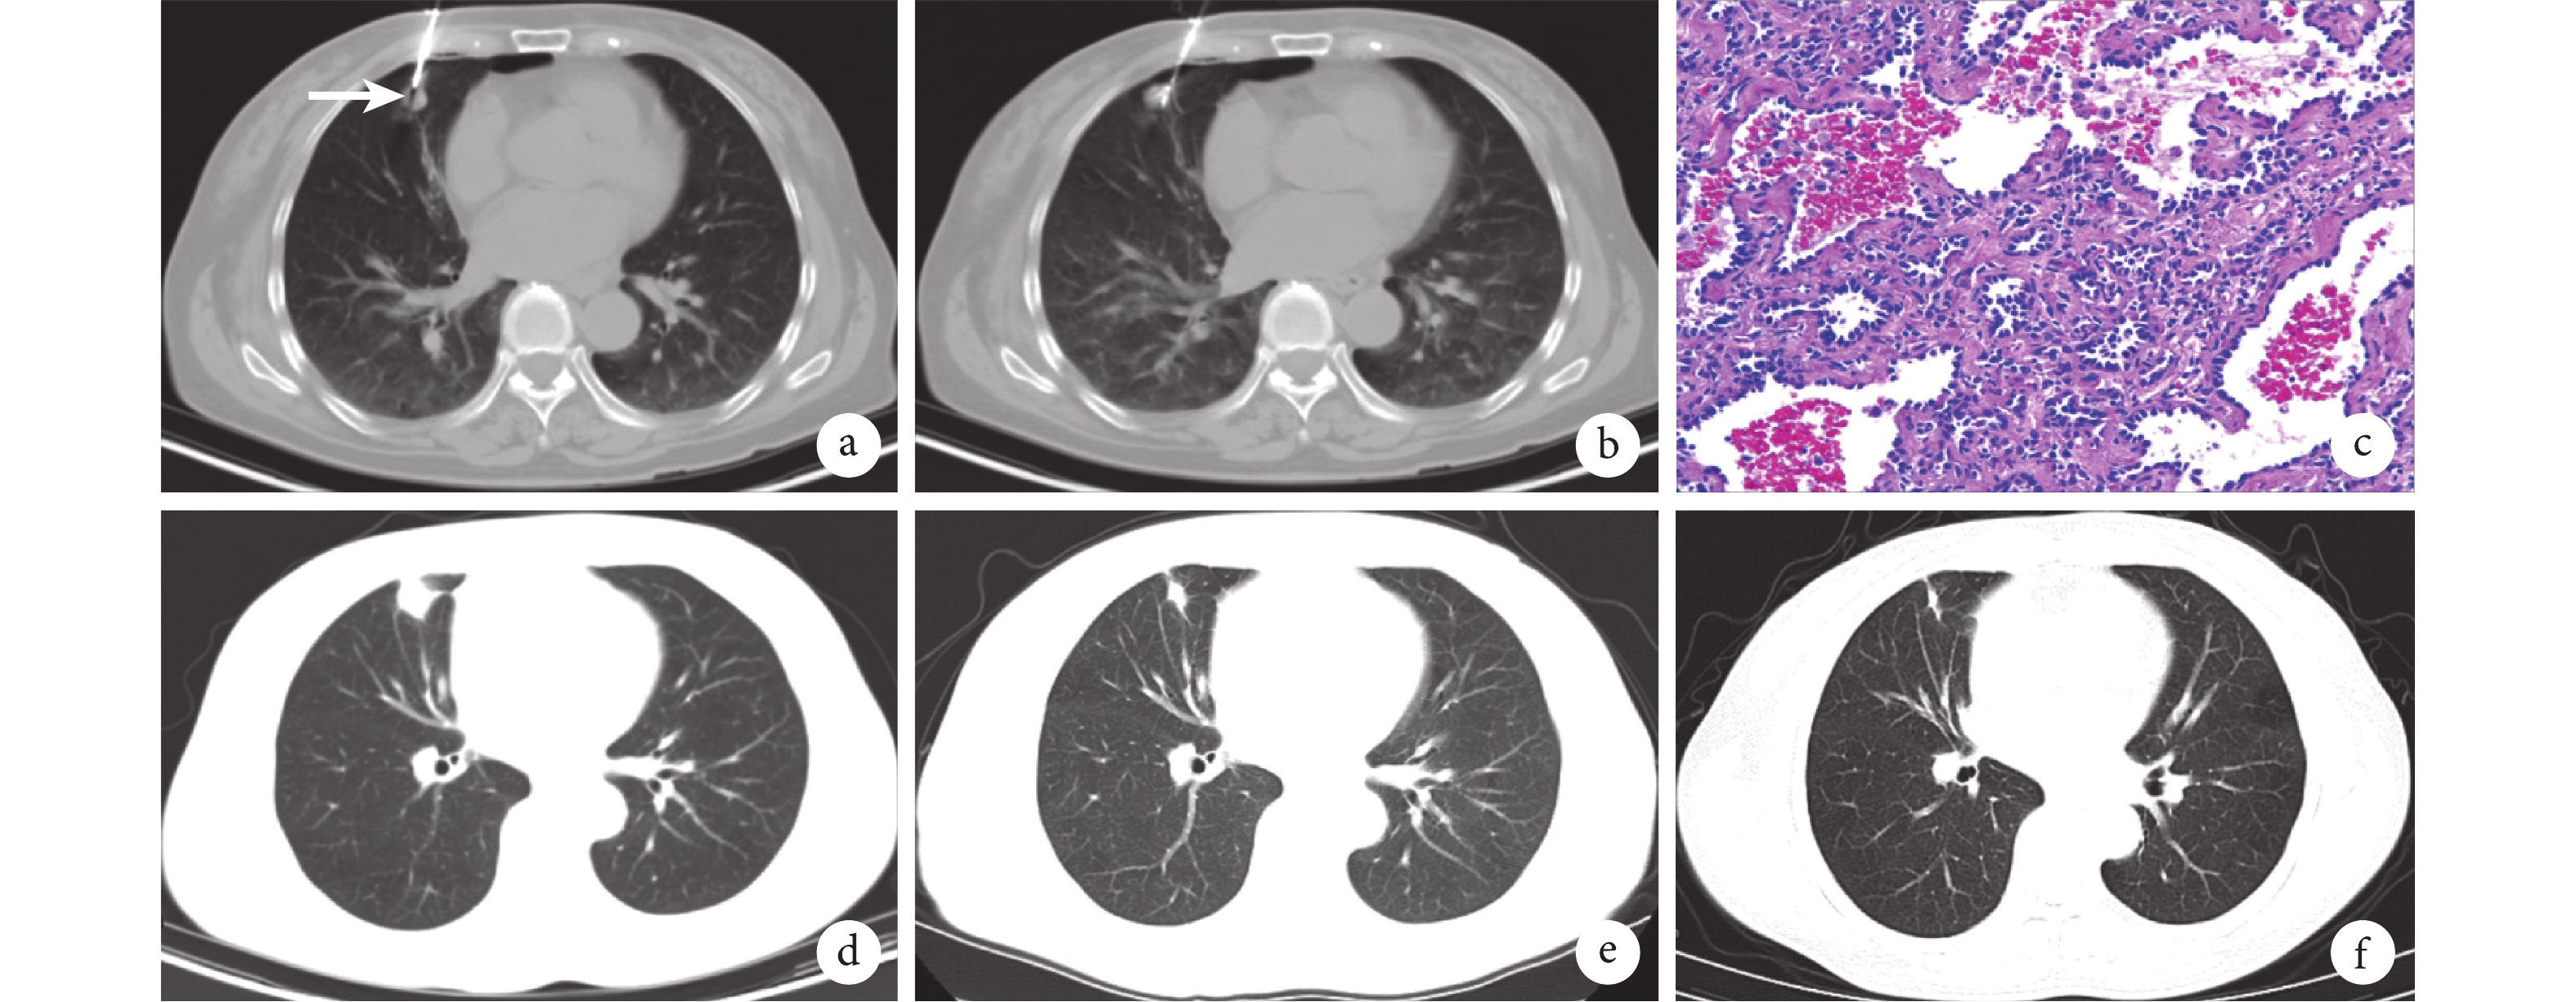

圖1

CT 及病理結果圖

患者,女,76 歲,發現右肺結節 2 個月入院,行活檢同步射頻消融治療;a:術中套管針穿刺至病灶邊緣;b:活檢完畢后射頻消融,局部胸膜凹陷,少量氣胸,未予特殊處理;c:活檢組織鏡下病理(×200),示原位腺癌;d:術后 1 個月復查,病灶局部增大;e:術后 6 個月復查,病灶較前明顯縮小;f:術后 12 個月復查,局部呈纖維灶,提示損毀完全

21 例患者共計 24 個病灶行 CT 引導經皮穿刺活檢同步射頻消融治療,入組患者均順利完成手術,手術時間(含麻醉誘導、蘇醒時間)為 60.0(57.5,92.5)min。術后即刻行 CT 掃描,所有消融區域均表現為局部周圍滲出伴有密度增高,呈“暈”征表現。4 例(19.0%,4/21)患者存在少量氣胸/胸膜皺縮,未予處理,觀察后自行好轉;見圖 1。1 例(4.7%,1/21)患者出現張力性氣胸,即刻行胸腔閉式引流,引流后 3 d 復查,氣胸好轉,拔除引流管。所有患者圍手術期無其它嚴重并發癥,順利出院。